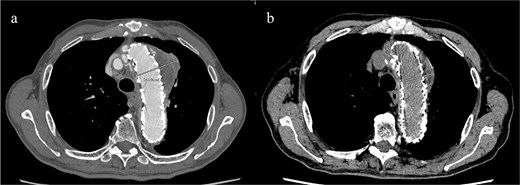

Given the ongoing hemoptysis, presumed aneurysmal expansion due to an occult endoleak, and the absence of any other obvious causes of hemoptysis, we determined that intervention for the aneurysm was necessary. TEVAR was performed using a right femoral artery approach. Initial angiography did not reveal contrast leakage into the sac (Fig. 3a). A 34 × 34 × 200 mm Gore Conformable TAG stent graft (W.L. Gore & Associates, Flagstaff, AZ, USA) was deployed to cover the distal edge of the FET. The second stent graft, a 34 × 34 × 150 mm Gore Conformable TAG stent graft, was deployed overlapping the first graft immediately after the left subclavian artery branch to cover the entire length of the FET (Fig. 3b). Considering the proximal migration, a type Ib endoleak was deemed the most likely cause. However, the possibility of a type III endoleak from the graft was also considered, so the stent graft was deployed to cover the entire area. The patient’s hemoptysis resolved completely postoperatively. A follow-up CT 2 years later showed a reduction in the aneurysm size from 56 to 44 mm (Fig. 4).

(a) Contrast-enhanced CT performed soon after TEVAR showing an aneurysm diameter of 56 mm. (b) Two years later, contrast-enhanced CT showing a reduction in the aneurysm diameter to 44 mm.